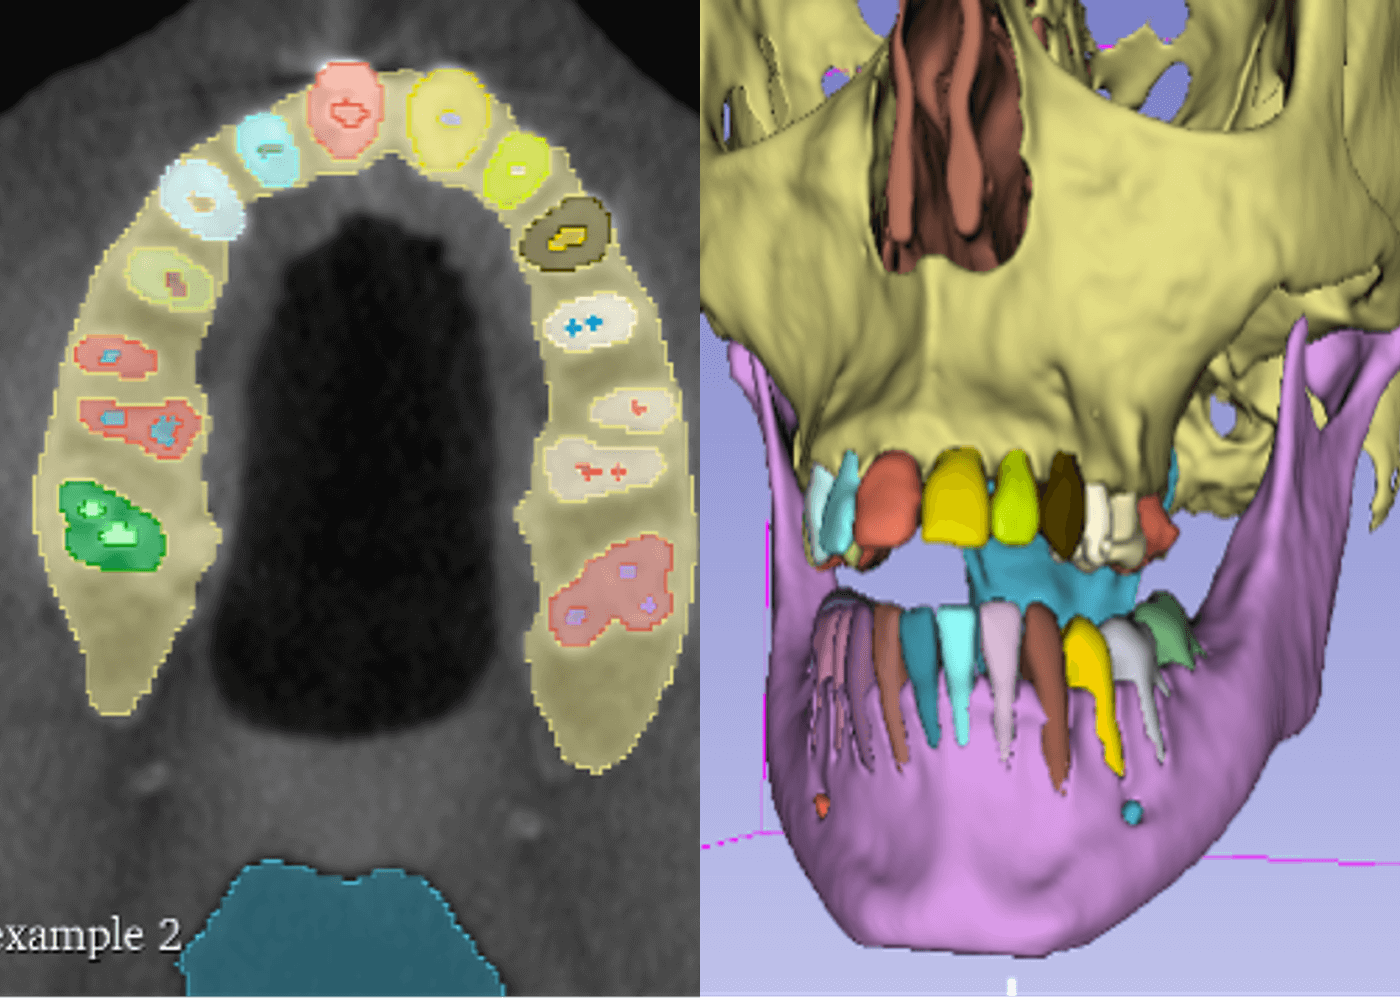

Dental cone beam CT structures segmentation